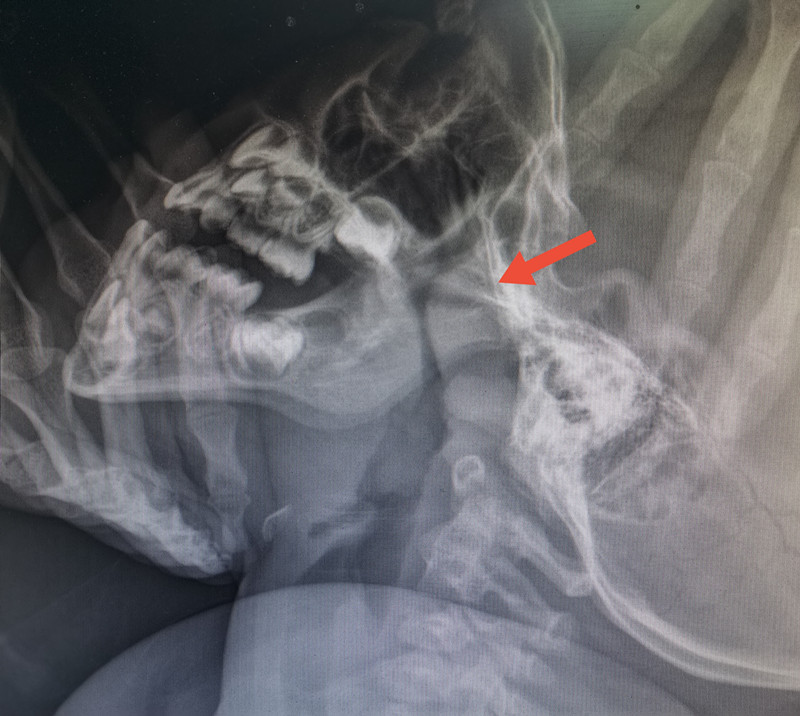

的确能。孩子睡觉时,正常闭着嘴用鼻呼吸时,口腔没有气流通过,舌头很自然就在口腔顶部。长时间张口呼吸,气流冲击硬腭(上牙膛),用力吸气时,面部肌肉收缩,致使面骨发育发生障碍,如颌骨变长、腭骨高拱、牙列不齐、上切牙突出、唇厚、缺乏表情等。这就是腺样体面容。

主要原因是呼吸不通畅。儿童时期易患上呼吸道感染(如急性鼻炎、急性扁桃体炎等)、过敏性疾病(如过敏性鼻炎),若反复发作,腺样体可迅速增生肥大,阻塞后鼻孔、加重鼻阻塞、阻碍鼻腔引流,鼻炎鼻窦炎分泌物又会刺激腺样体,使之继续增生,形成互为因果的恶性循环。肿大的腺样体堵住呼吸要道,孩子只能张嘴呼吸,久而久之就会形成上面所说的“腺样体面容”。